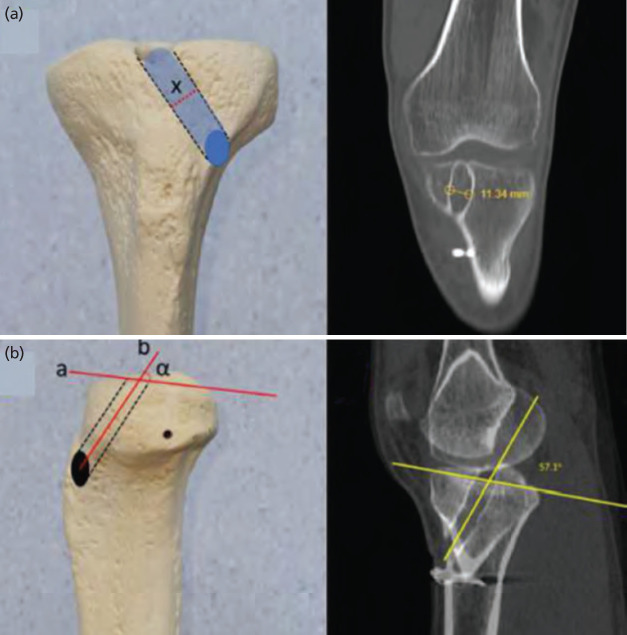

Introduction: Anterior cruciate ligament (ACL) reconstruction is a commonly performed surgical procedure. The objectives of this retrospective comparative study are (1) to evaluate the obliquity, size and the intra-articular aperture shape of the tibial tunnel in patients operated with an anteromedial portal technique, and (2) to determine their possible relation with revision surgery.

Material and methods: Patients operated for a primary ACL reconstruction between 2014 and 2018 were eligible. All patients of primary and revision ACL fulfilling the inclusion criteria were assessed for presence of a knee CT scan within one month of surgery and at least three years of follow-up. Several radiological parameters were measured for the study, among which: Tunnel height, Coronal tunnel angle, Maximal tunnel width and Sagittal tunnel inclination. Multivariate analyses were performed to identify parameters correlated with revision.

Results: Mean age of the primary group was 30.5±8.4 versus 29.4±8.0 of the revision group. The majority of patients were males in both groups (n=33, 76.7% and n=38, 95.0%, respectively). A longer diameter of the intra-articular ellipse (p=0.005) and an increased mid-tunnel to TT distance on the axial plane (p=0.006) were significantly correlated with revision. A ROC curve analysis determined a cut-off value of 27.9mm from the tubercle was an optimal entry point.

Conclusion: A greater distance between the mid-point of the tibial tunnel entrance and the centre of the tibial tubercle is linked to a higher risk of revision. An elongated elliptic shape in the antero-posterior plane also correlates with revision risk.